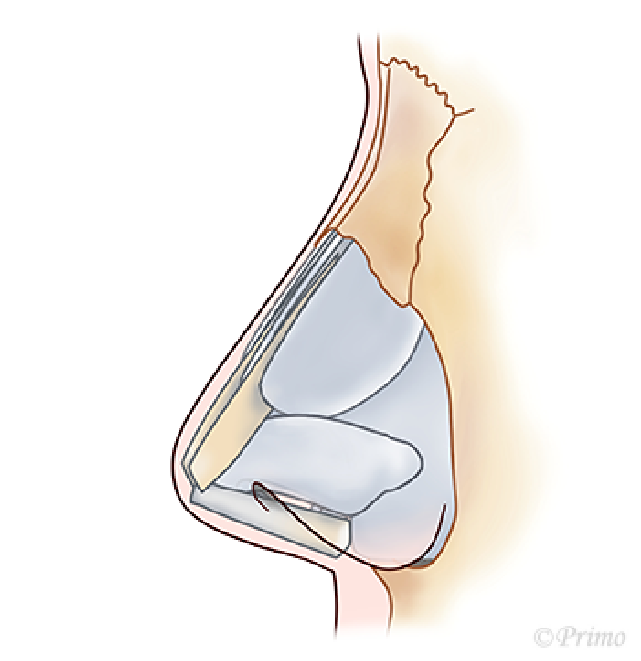

アプローチは経鼻柱切開(オープンアプローチ)から、術野を広く展開し、確実に操作を行います。鼻中隔軟骨に移植軟骨を組み合わせ延長し鼻の向き、高さを変えていきます。ご希望に応じ鼻の脂肪を部分的に除去し細っそりとさせたり、インプラントによる隆鼻術を併用し、より印象的な鼻に変化させます。鼻柱の傷あとはあまり目立ちません。

日本人はもともと鼻中隔軟骨や、鼻翼軟骨といった鼻の骨格が小さく、そして弱い傾向があります。そのため上向きの鼻であったり、低い鼻であったり、団子鼻であったりする人が多くみられます。

鼻先にただ軟骨を乗せるように移植しても鼻翼軟骨が支えきれず変形し、思うように鼻先を高くできない場合が多いようです。また乗せた軟骨が不安定なため、上下、左右に移動しやすくなります。

青い部分が移植した軟骨です。この軟骨の固定により、鼻の高さ、細さ、向きが大きく調節できます。